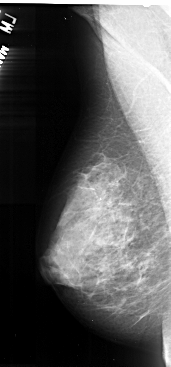

A_1037_1.RIGHT_MLO

RIGHT_MLO LINES 5161 PIXELS_PER_LINE 2566 BITS_PER_PIXEL 16 RESOLUTION 42 OVERLAY